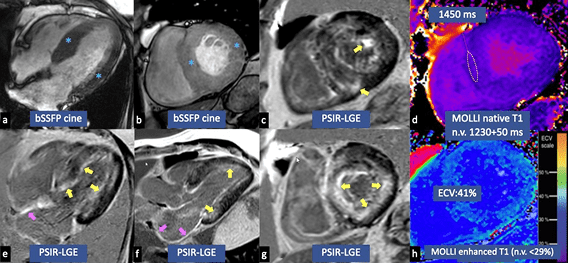

ECHO4

- hypertropher Phänotyp mit infiltrativen Merkmalen

- eingeschränkte LV-Füllung mit LV-Wandverdickung

- Reduktion des globalen longitudinalen Strain